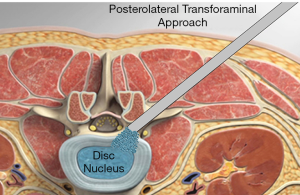

PETOFPC technique innovatively sets screws from posterior corner in lumbar spine in a regular 7.5-mm diameter channel. PETOFPC is also performed in the posterolateral transforaminal approach (Figure 18). A cylindrical sheath with an outer diameter of 7.5 mm were inserted in sequence. Through the sheath alone or the endoscope, the intervertebral disk and cartilaginous endplate were removed while confirming through percutaneous endoscopic observation that no cartilage remained. At the completion of the endplate preparation, the new integrated fixable and fused interbody cage was inserted into the intervertebral space (16). Before the new integrated fixable and fused interbody cages were expanded, we should clearly expose the screw entry point in posterior corner. The screw entry point is the bony area between the pedicle and the endplate. When intervertebral height was restored, the two wings of new integrated fixable and fused interbody cage splay to the sides and fit to posterior corner in lumbar spine (Figure 19). In the single 7.5-mm channel, endoscopic visualization was used to monitor placing screws to make the new integrated fixable and fused interbody cage fixed in lumbar spine. The angles of screw placement were made up of inward inclined angle, head tilt angle and tail tilt angle, namely c1, c2, c3, a1, a2, a3, b1, b2 and b3, all which was measured and analyzed in this study.